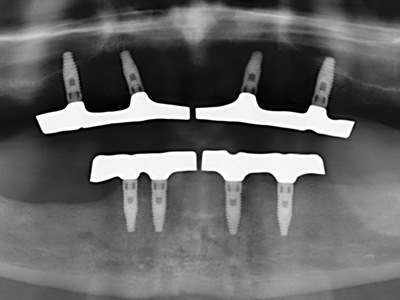

As shown in the past, basically any bone surgery procedure represents a possible indication for piezosurgery. Thus preparation of the mobile segment in distraction osteogenesis (Fig. 23-25) and sandwich osteotomy uses special attachments without endangering the blood supply to the crestal section, which is essential for the success of both techniques (Gonzalez-Garcia, Diniz-Freitas et al. 2008).

For removal of an implant, a vestibular bone cover that is replaced after removal of the implant screw can be prepared to retain the contour of the alveolar ridge.

There are additional applications in sinus surgery. Pathologies and foreign bodies can be removed from the sinus after concentric preparation of a generally trapezoid bone cover in the facial sinus wall. The bone cover is repositioned on conclusion of the intra-antral operation component and secured by wedging or adaptive sutures to prevent dislocation.

Purely orthodontic indications include orthognathic surgery, genioplasty (Fig. 27-30) and orbital decompression in patients with advanced endocrine orbitopathy as a result of Basedow’s disease (Ponto, Zwiener et al. 2014). Piezo devices are also used in maxillofacial surgery and to remove tumours at the base of the skull in various hospitals.